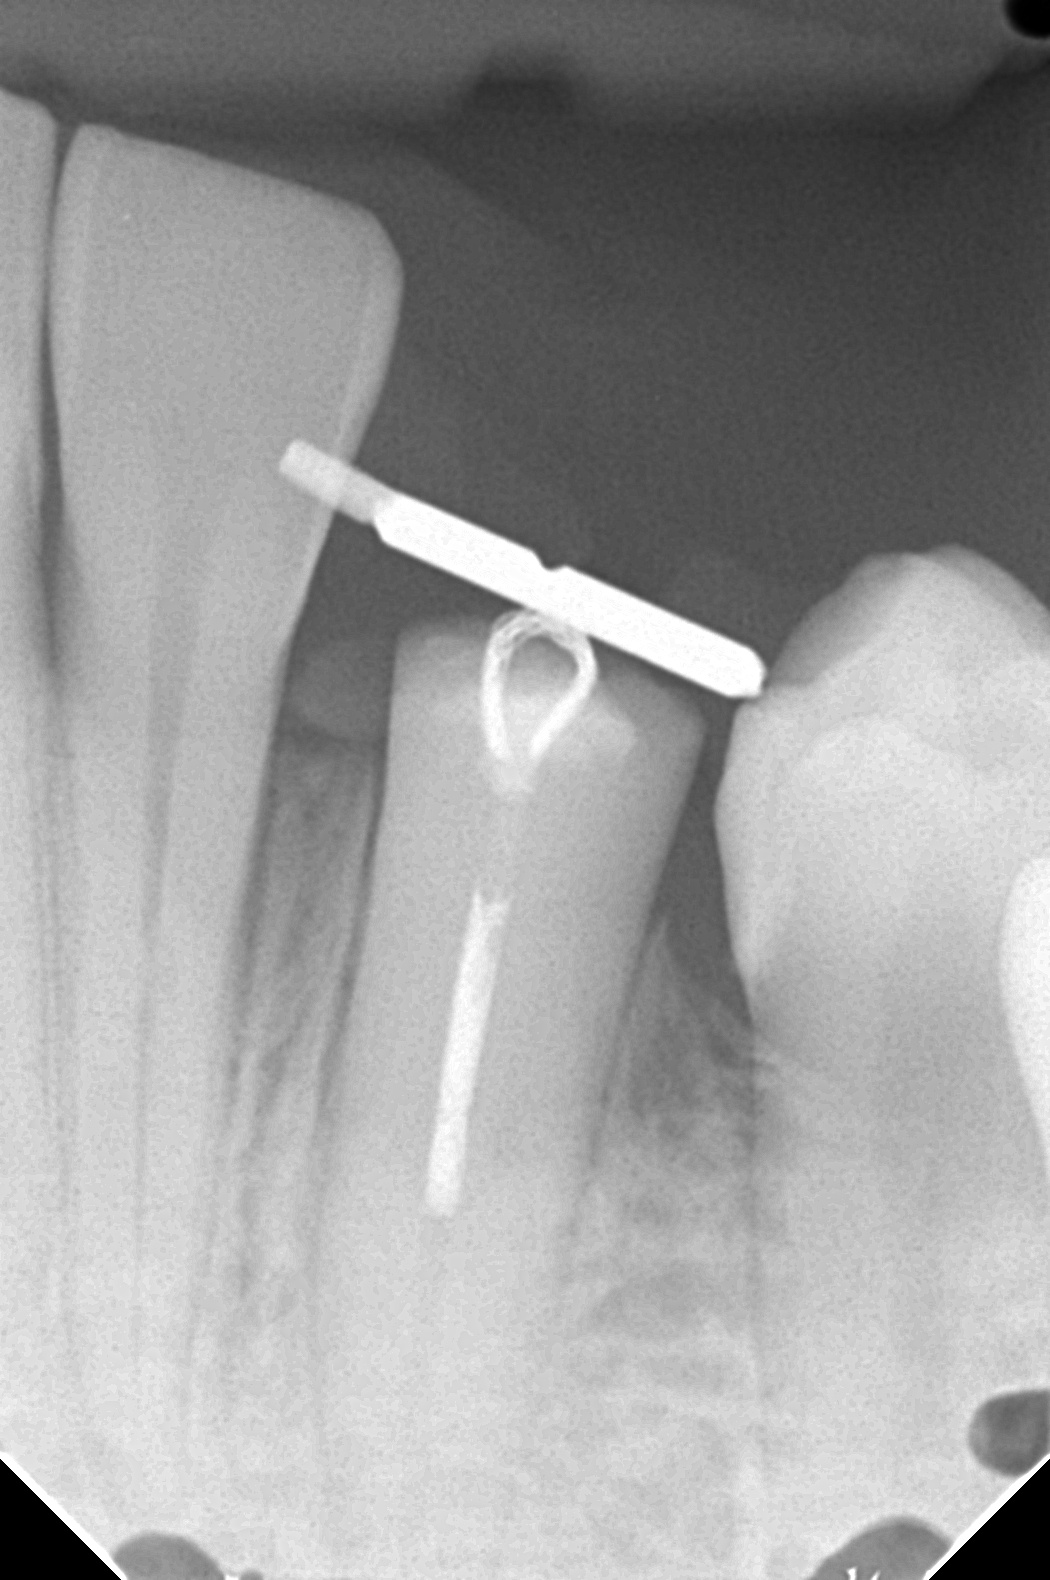

下の写真は、実際に隣の歯にワイヤーを渡してゴムの力で引き上げている口腔内の様子です。

下のレントゲン写真は、矯正的挺出が完了した後の状態です。挺出前のレントゲンと比較すると、骨のラインより上に歯根がしっかりと出てきているのが確認できます。